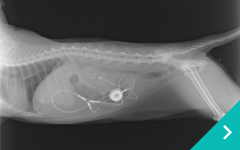

SUBシステム

SUB

システム